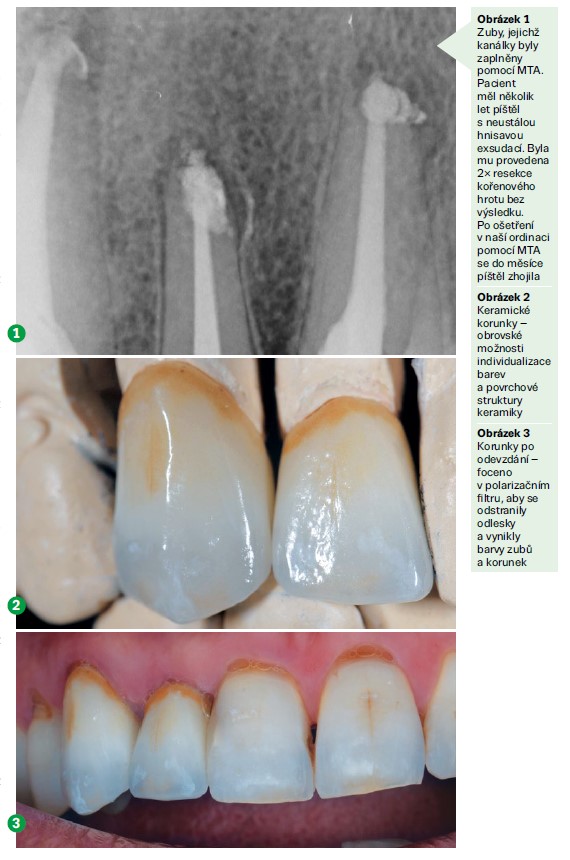

Další oblastí, kam stomatologie směřuje, je estetika. Neustále se posunují a zlepšují materiály, které se v ordinacích používají. Například materiál MTA (mineral trioxide aggregate), který se používá při ošetřování kořenových částí zubů, napomáhá hojení v jejich okolí takovým způsobem, že je dnes možné zachránit mnohem větší procento zubů než před několika málo lety.

Největší změny se dějí mimo ústa pacienta, při změnách materiálů a postupů. Například intraorální scaner může mít dnes lékař v ordinaci, ale také může být v laboratoři. Jako zubní technik dokáži ocenit staré postupy zhotovování zubních náhrad. I když byly jednoznačně pracnější a pomalejší, měly své kouzlo a zubní technik si připadal spíš jako zlatník, kterému se rodí pod rukama šperk na míru pro konkrétního člověka. V dnešní době je zubnímu technikovi vracena zasloužená vážnost, ale vše je rychlejší. Tomu se přizpůsobují i materiály, aby se daly dobře vyfrézovat nebo vytisknout. Postupně se upouští od konstrukcí z kovu, jelikož jeho zpracování je náročné a frézování trvá dlouho. Frézují se jen konstrukce, kde kov zatím nelze nahradit, ale bohužel jsou drahé. Levnější formou zpracování je tisk kovových konstrukcí, kdy se jednotlivé vrstvy spékají laserem a pomalu vzniká celý výrobek po tenkých vrstvách. Na korunky se nyní používají konstrukce z oxidu zirkoničitého (ZrO2). Tento materiál je vysoce odolný a jen s drobným individuálním dobarvením poskytuje skvělé estetické výsledky. U snímatelných náhrad se prosazuje vysokoteplotní plast PEEK, který lze dobře frézovat a má vazbu k materiálům.